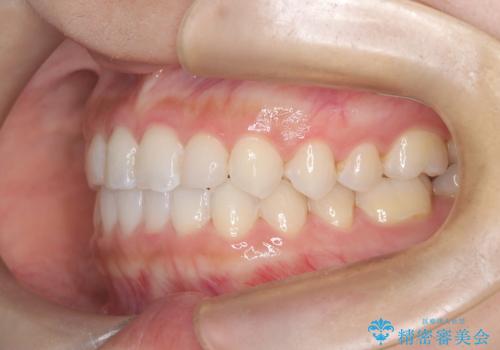

- 前歯の凸凹を主訴に来院された患者様です。

カウンセリング時に、側切歯が矮小歯であることを指摘したところ、適切な幅径での修復を希望されました。

インビザラインを用い、計画通りに歯並びを改善することができました。

矮小歯の幅径を大きくすることで、より理想的な噛み合わせを作ることができます。